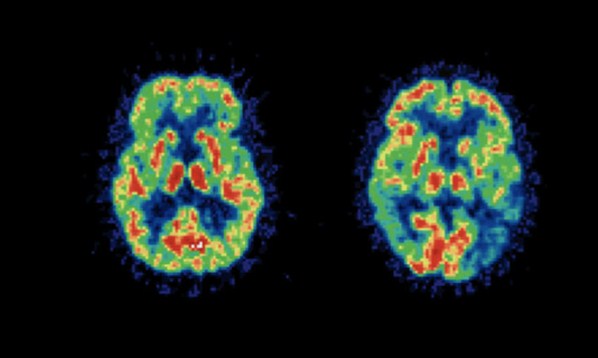

ΤΟ ΑΛΚΟΟΛ ΔΕΝ ΚΑΤΑΣΤΡΕΦΕΙ ΤΑ ΕΓΚΕΦΑΛΙΚΑ ΚΥΤΤΑΡΑ (ΕΥΤΥΧΩΣ..!)

Πόσες φορές δεν το έχετε ακούσει αυτό από τη μητέρα σας, τον πατέρα σας ή τους δασκάλους όταν ήσασταν μικρός; Το ενδιαφέρον είναι πως αυτός ο μύθος έχει διαιωνιστεί από την ίδια ομάδα ανθρώπων που επιμένουν πως έχοντας αλκοόλ μέσα στο αίμα μπορεί να έχει σαν αποτέλεσμα να πιάσετε φωτιά. Ευτυχώς, πρόσφατες έρευνες έχουν δείξει πως μία μέτρια (ναι, μέτρια) κατανάλωση αλκοόλ μπορεί να βελτιώσει την λειτουργία του εγκεφάλου.